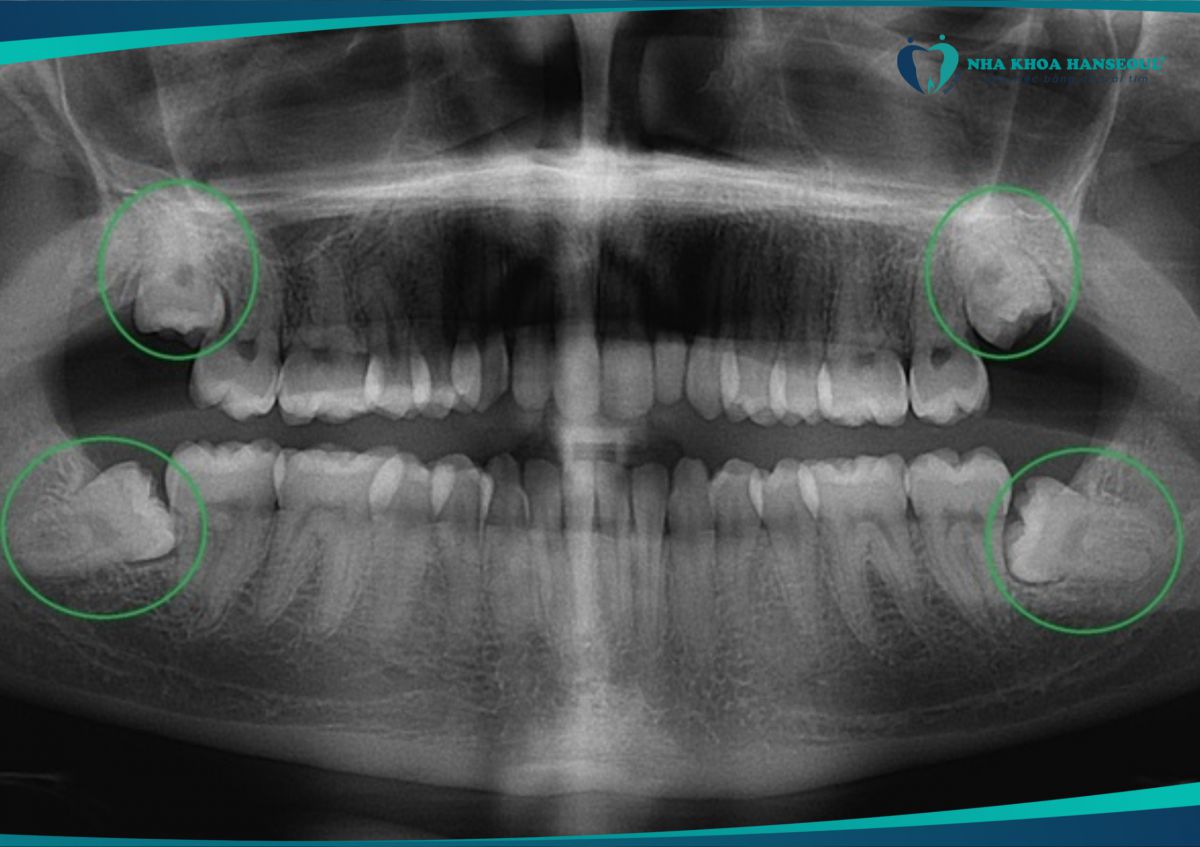

Vì vậy, ngay cả khi răng số 8 không đau, bạn vẫn nên chụp X-quang để kiểm tra vị trí mọc và nghe tư vấn từ nha sĩ.

8 Răng mọc lệch, mọc ngầm

- Nếu chụp X-quang thấy răng khôn mọc xiên, đâm ngang hoặc nằm ngầm dưới nướu, nha sĩ sẽ khuyên nhổ sớm.